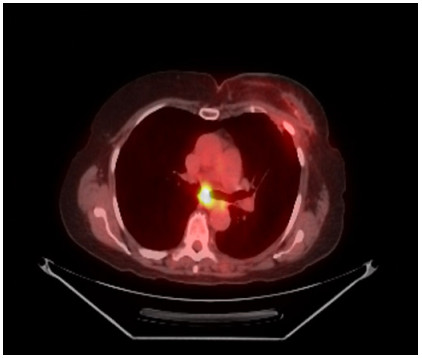

Abstract: Squamous cell carcinoma of the anal canal remains rare, with metastatic disease even less commonly reported. We present a case of a patient with both a prior history of squamous cell carcinoma of the anal canal as well as breast cancer, who was without evidence of disease for 1 year. She was subsequently found to have FDG-avid mediastinal lymphadenopathy, initially assumed to be related to her more recent breast cancer. However, a biopsy confirmed recurrent anal cancer, with HPV infection. This represents a novel site of spread for anal cancer, one not yet reported in the literature.